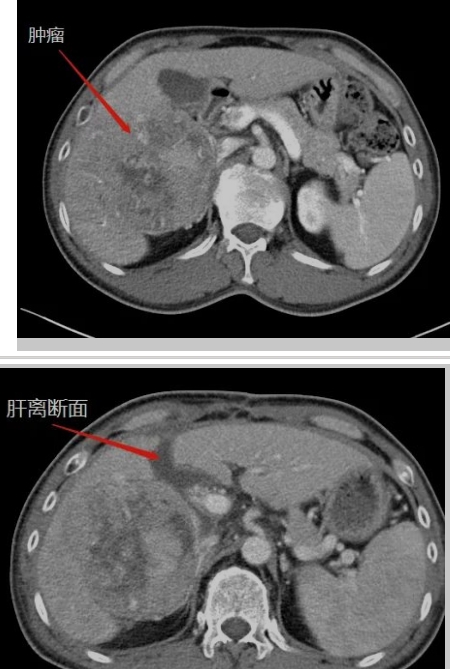

在生命的長(zhǎng)河中,每個(gè)人都在與時(shí)間賽跑,與命運(yùn)抗?fàn)帯6鴮?duì)王晚期肝癌患者來(lái)說(shuō),這場(chǎng)賽跑尤為艱難,這場(chǎng)抗?fàn)幐裢怏@心動(dòng)魄。還記得四年半以前,當(dāng)40多歲的王先生被確診為晚期肝癌伴乙肝、肝硬化時(shí),絕望的陰霾籠罩著整個(gè)家庭。對(duì)王先生來(lái)說(shuō),那是一段黑暗的日子,對(duì)未來(lái)的恐懼,對(duì)生命的不舍,尤其對(duì)年幼的孩子的不舍,讓他...